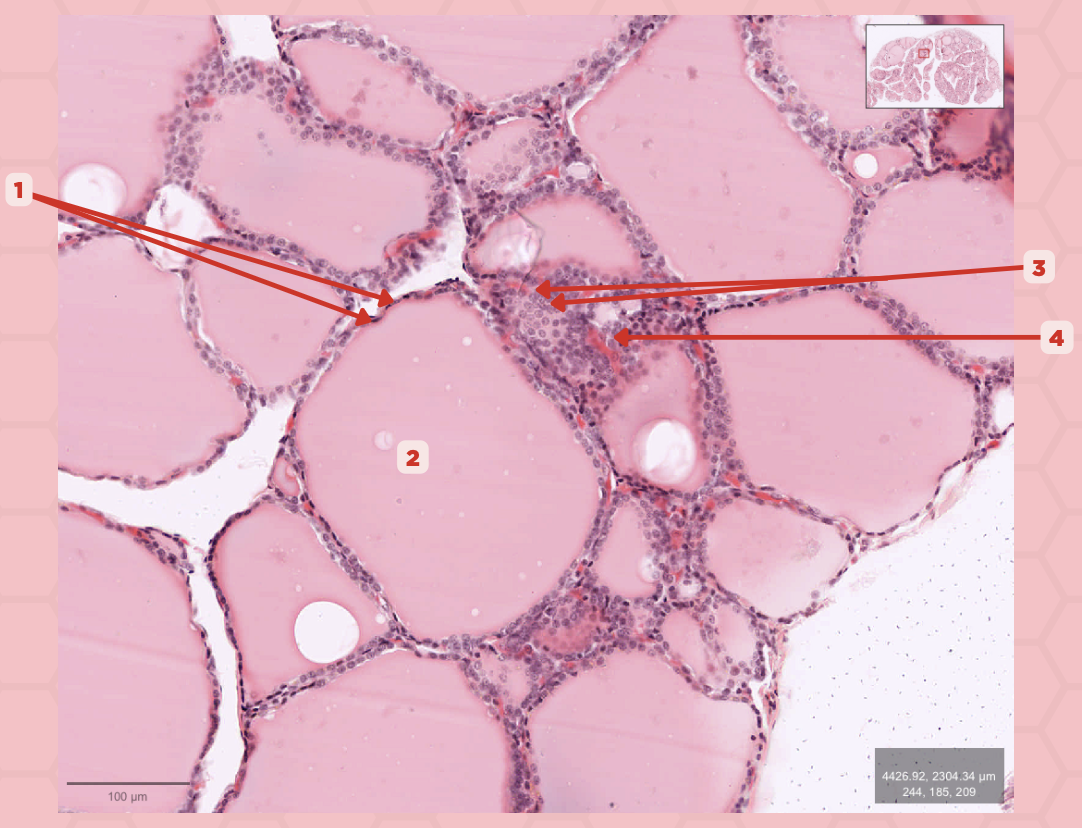

Thyroid

Identify the specimen.

Lobules

Identify the structure labeled as 1.

Follicles

Identify the structure labeled as 2.

T3 and T4 Hormone

What type of hormone is being secreted by the pointer #1?

Follicular Cells

Identify the structure labeled as 1.

Colloid

Identify the structure labeled as 2.

Parafollicular Cells

Identify the structure labeled as 3.

Capillary

Identify the structure labeled as 4.